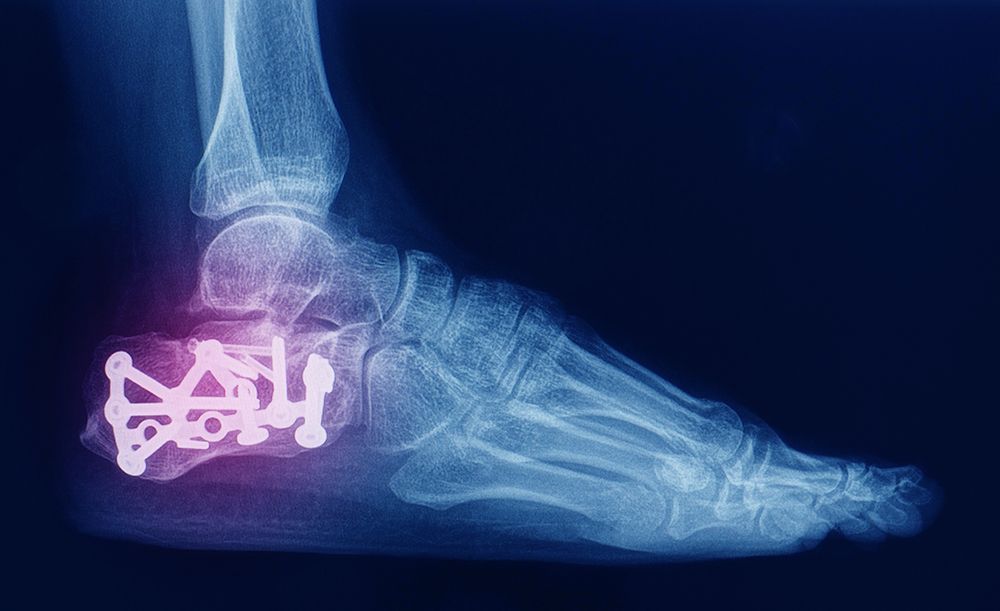

For patients with severe ankle arthritis or damage that limits mobility and causes chronic pain, ankle implant or replacement surgery can be a life-changing solution. At Rock River Foot & Ankle Clinic, our board-certified podiatrists specialize in advanced surgical techniques designed to restore natural movement and relieve persistent discomfort.

We begin with a detailed evaluation of your ankle joint using diagnostic imaging to assess bone structure, joint alignment, and cartilage health. Based on your condition, we may recommend a total ankle replacement or implant procedure that preserves as much natural motion as possible while stabilizing and supporting the joint.